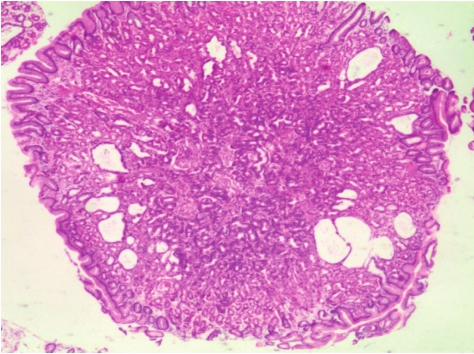

增生性息肉(hyperplastic polyp)是胃黏膜反复损伤修复导致的胃小凹上皮过度增生性病变(图3-11),最多见,约占全部胃息肉的85%,常发生于老年人。

好发于胃窦部,常多发,直径一般小于2.5cm。表面光滑,有蒂或无蒂。

胃小凹上皮增生肥大,使得胃小凹伸长、扭曲、扩张变形,并可延伸至间质(图3-11)。增生的胃小凹上皮无明显异型,有或无肠上皮化生。息肉可包括幽门腺、主细胞和壁细胞。极少数伴有肠上皮化生和高级别上皮内瘤变者可发展为癌。

图3-11 增生性息肉

胃小凹伸长、扭曲、扩张变形,固有层间质有不同程度的水肿和炎症反应。